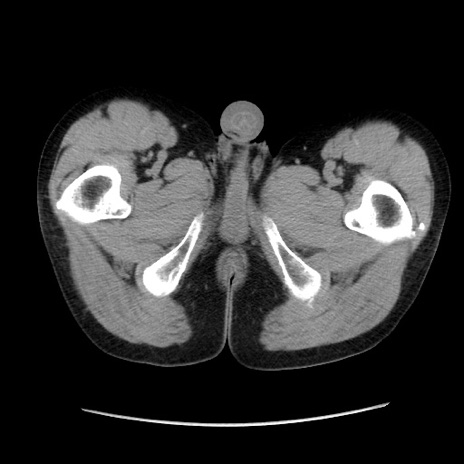

症例37(横断像)

冠状断像

【症例】40歳代 男性

【主訴】腹痛

【現病歴】4時間ほど前に電車に乗車中に臍部上より腹痛出現。徐々に増悪し起立困難となり、救急外来受診。生ものは数日食べていない。今朝お雑煮を食べた。

【身体所見】BT 36.8℃、BP 117/84mmHg、HR 91/min、SpO2 97%、苦悶様、腹部:臍上部広範囲圧痛あり、反跳痛±

【データ】WBC 8100、CRP 0.03